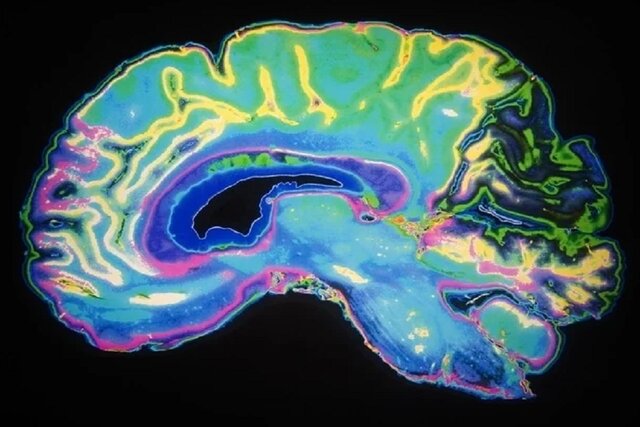

کشف مسیر انتقال ریزذرات مضر از ریه‌ها به مغز

یک گروه بین‌المللی از پژوهشگران، مسیر مستقیمی را بین ریه‌ها و مغز کشف کرده‌اند که عامل انتقال ریزذرات مضر از ریه‌ها به مغز است.

به گزارش ایسنا و به نقل از نیوز مدیکال نت، یک پژوهش بین‌المللی نشان می‌دهد که تنفس در هوای آلوده می‌تواند انتقال ذرات سمی از ریه‌ها به مغز را از طریق جریان خون در پی داشته باشد و به بروز اختلالات مغزی و آسیب‌های عصبی منجر شود.

دانشمندان، یک مسیر مستقیم احتمالی را کشف کرده‌اند که ذرات ریز استنشاقی از طریق گردش خون از آن استفاده می‌کنند. ذرات پس از رسیدن به این مسیر، برای مدت طولانی‌تری در مغز باقی می‌مانند.

یک گروه بین‌المللی از متخصصان "دانشگاه بیرمنگام"(University of Birmingham) انگلستان و موسسات پژوهشی چین، در این پژوهش مشترک، ذرات ریز مختلفی را در مایعات مغزی-نخاعی انسان یافته‌اند که از بیماران مبتلا به اختلالات مغزی گرفته شده بودند. آنها فرآیندی را کشف کردند که ممکن است به پایان یافتن حضور ذرات سمی در مغز بیانجامد.

وی افزود: داده‌های این پژوهش نشان می‌دهند تعداد ریزذراتی که ممکن است با کمک جریان خون از ریه‌ها به مغز برسند، تا هشت برابر بیشتر از تعدادی است که مستقیما از بینی عبور ‌می‌کنند. این پژوهش، شواهد جدیدی را در مورد ارتباط بین آلودگی هوا و اثرات مضر چنین ذراتی بر مغز نشان می‌دهد.

این گروه پژوهشی دریافتند که ذرات استنشاق‌شده می‌توانند پس از عبور از "سد خون-هوا"(Blood–air barrier)، به جریان خون وارد شوند. آنها در نهایت به مغز می‌رسند و به سد خونی مغز و بافت‌های اطراف آن آسیب می‌رسانند. زمانی که ذرات به مغز وارد می‌شوند، به سختی می‌توان آنها را پاکسازی کرد. بدین ترتیب، ذرات برای مدت طولانی‌تری نسبت به سایر اندام‌ها، در مغز باقی می‌مانند.